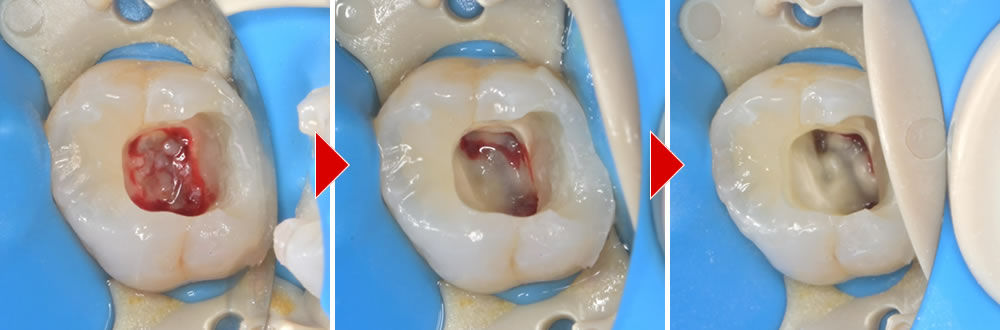

ラバーダム防湿を行い、隔壁(歯の補強)を立てます。

歯髄温存療法(断髄法)の実施

感染を起こしている歯髄部分のみを除去し、消毒と止血を行いました。

MTAセメントを使用し、断髄処置を行いました。